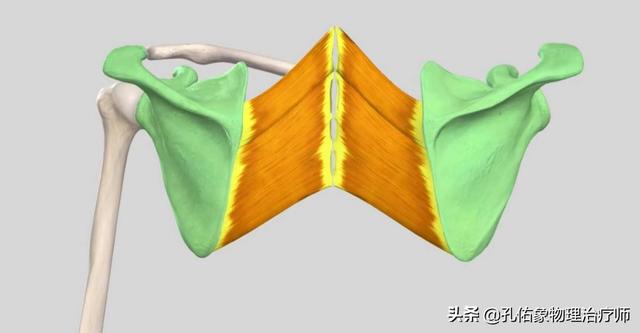

Si vous regardez de près, vous verrezCe trapèze.inclureBase du crâne, cou, épaules et dosLes muscles trapèzes des deux côtés sont étroitement liés et forment ensemble une structure rhomboïde, qui est essentielle au maintien de l'équilibre de la colonne vertébrale.Stabilisation du dosIl joue un rôle très important dans l'accomplissement de multiples activités au niveau du cou, des épaules et du dos.Le muscle trapèze est divisé en faisceaux supérieur, moyen et inférieur, et les différentes parties de la contraction permettent d'effectuer des mouvements différents。

Ce n'est qu'un seul muscle, il y en a beaucoup d'autres dans le cou, les épaules et le dos.chairqui sont toutes reliées entre elles, y comprisFascia sous la peauC'est aussi une seule et même chose, on ne peut pas séparer le cou, les épaules et le dos, je crois qu'il faut le comprendre.